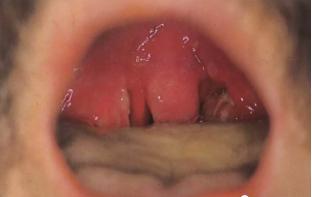

六.杨梅舌或草莓舌。